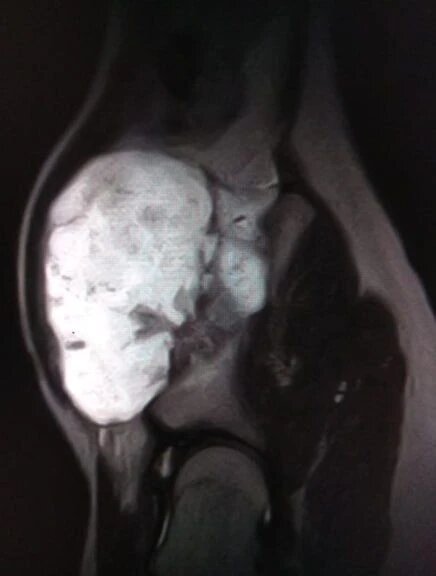

В областной детской клинической больнице №2 прооперировали подростка с редким диагнозом «экзостозная хондродисплазия». У мальчика образовался костно-хрящевой нарост на подвздошной кости размерами 12 на 9 на 7 сантиметров. Образование вызывало боль, мешало движению и угрожало тазобедренному суставу.

Операцию провела бригада под руководством заведующего отделением ортопедии Александра Птицына. Хирургам предстояло удалить экзостоз в сложной анатомической зоне, не задев сосуды, нервы и зоны роста кости. Вмешательство прошло успешно: нарост удалён полностью.